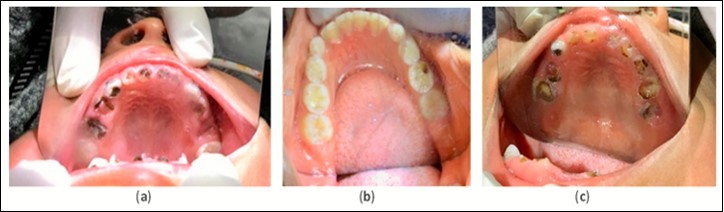

The treatment protocol involved carefully cleaning with a toothbrush and thoroughly drying all cavitated caries lesions using compressed air, followed by the application of 50% SN (Gordon Laboratories) by scrubbing with a microbrush then covering with FV (Centrix, Fluorodose) to protect from saliva contamination. The lesions received three separate treatments over two weeks. This protocol of three treatments was repeated at three and six months. Intraoral images were collected for the maxillary and mandibular arches for all children at each time point (Figure 2 and Figure 3). Emergency services were both conducted on-site and via referral to local professionals. Simple extractions of abscessed teeth with local anesthesia were done on site. Referrals to the local Ministry of Health Dental Clinics were done in cases where endodontics and complex restorative procedures were necessary.

Figure 2.Example pre-treatment intraoral images for Ecuador (a), Ghana (b), and Bolivia (c) at initial evaluation.

The same materials, treatment frequency, and protocol used in Ecuador was replicated in Ghana. Evaluation and treatment were conducted at initial examination and at 12 months. Intraoral images of maxillary and mandibular arches were collected for all patients at each time point (Figure 2 and Figure 3) . At the 12-month visit, the Ghanaian dentist Dr. Ama Ofosu Appiah, our partnering individual, joined the Shoreview team and participated in the project. Her role was to assist in treatment and outcomes documentation. The Shoreview team calibrated this dentist in-person via hands-on training for the application protocol and cavitated caries lesion arrest assessment.

Emergency services were provided on-site where abscessed teeth were removed with local anesthesia at the school. School officials were instructed to find a nearby dentist to provide endodontics and complex restorative procedures when necessary. A surprising finding in this population was that most children had excellent oral health with very few cavitated caries lesions in their dentitions (Figure 2 and Figure 3).

The treatment protocol used in Bolivia differed from what was used in Ecuador and Ghana. The protocol that was used involved the following: carefully clean the cavitated caries lesion using a toothbrush, thoroughly dry using compressed air, apply 38% SDF by scrubbing with a microbrush applicator, then cover with FV to prevent saliva contamination. Since access to electricity was available at the school, mobile dental equipment with a reliable compressed air source was available. This protocol was repeated at the timepoints of 6, 12, 18, 24, 30, and 36 months. Intraoral images of maxillary and mandibular arches were collected for all patients present at 36 months (Figure 2 and Figure 3). Emergency services were both conducted on-site and via referral to local professionals. If a tooth showed signs of being abscessed, it was extracted by Smiles Forever Clinic dentists on site using local anesthesia. Endodontics and complex restorative procedures were referred out to the local hospital dental department or the Smiles Forever Clinic in Cochabamba.

Although these three humanitarian community outreach programs were not conducted as research, and should be looked at as separate case reports, careful attention to data collection was made at initial examination and at all follow up encounters. The Shoreview Dental, LLC team exclusively conducted data analysis on outcomes data related to Ecuador and Ghana but collaborated with the Smiles Forever Foundation for data analysis related to Bolivia. Surface specific charting and maxillary and mandibular arch photos were taken at all timepoints in Ecuador and Ghana but only at 36 months in Bolivia. A determination of all cavitated caries lesion activity or arrest was recorded based on lesion color and surface hardness. A lesion was considered arrested if the color was black and the surface was determined to be hard using gentle tactile examination (Figure 3).12,15 The presence or absence of caries lesion related mouth pain was asked of the children themselves as well as their parents and teachers.

The results discussed below are derived from Table 1. Please review the table for a more comprehensive evaluation of outcomes. Pre-treatment intraoral image examples of cavitated caries lesions in Ecuador, Ghana and Bolivia can be found in Figure 2. An example of arrested cavitated caries lesions can be found in Figure 3. All charted information for all patients was stored securely and confidentially and data was anonymized before evaluation of outcomes.